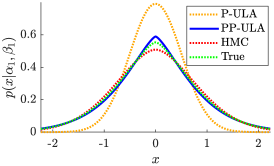

The convergence speed of Algorithm 3 is empirically observed for Simu1 and Simu2, as illustrated in Fig. 2, where we also display the results of the non-preconditioned P-ULA, for which and . Comparing P-ULA and PP-ULA on these simulated data allows us to study the effect of adding a preconditioner in the proposed sampling scheme. As reported in Table II, P-ULA needs more iterations and more time to converge than PP-ULA: the proposed method is 12.2 and 4.8 times faster than P-ULA on Simu1 and Simu2, respectively. In addition, from Table III and Fig. 3, we deduce that P-ULA is more biased than PP-ULA, which samples correctly the target distributions. Finally, as one can see in Fig. 2 and Table IV, P-ULA leads to lower PSNR, SSIM and OA values than PP-ULA. These results clearly emphasize the benefits of preconditioning in this example.

From Table II, PP-ULA is 5.7 and 6.6 times faster than HMC on Simu1 and Simu2 and has better mixing properties, as shown by the MSJ per second. Visual results from Fig. 4 and CNR values in Table IV show that the contrast obtained with PP-ULA is better than with competitors on Simu2, and is second best after P-ULA on Simu1. However, it should be noted that the PSNR and SSIM obtained on Simu1 with P-ULA are much lower than with the other methods. In addition, the PSNR and SSIM values from Table IV obtained with PP-ULA are equivalent or higher than all competitors for these two experiments. Visual segmentation results are shown in Fig. 5, and OA values can be found in Table IV. For these simulated images, more pixels are correctly labeled with PP-ULA than with competitors.